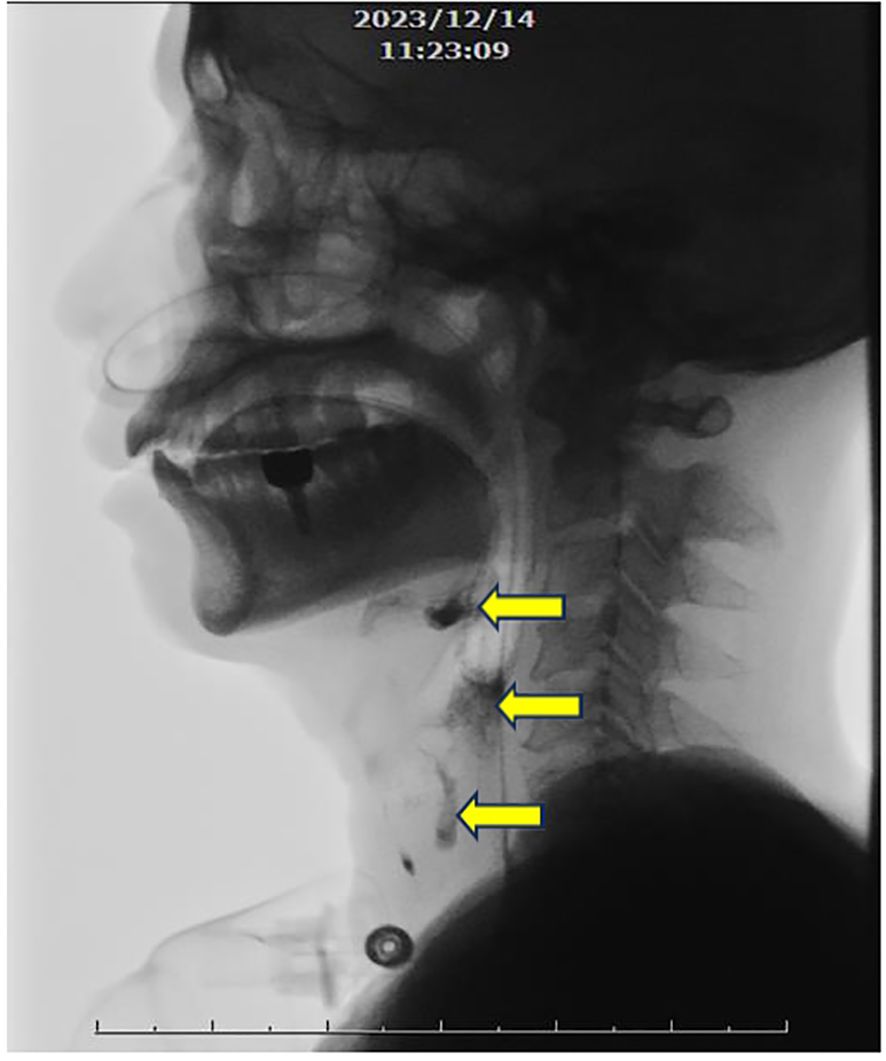

The patient was admitted to a hospital in Southeast Asia, and a contrast-enhanced brain MRI revealed nonspecific edematous change. A T2-weighted image revealed longitudinal hypersignal from anterior medulla to C1 spinal cord. (Figure 1) A CSF examination for infection returned negative results.

Figure 1. (A) Contrast-enhanced T2-weighted MRI in the longitudinal view, revealing a longitudinal signal increase extending from the level of medulla to C1. (B) Signal increase at the anterior portion of the medulla (arrows).

Initial investigations included contrast-enhanced MRI of brain, which showed nonspecific edematous changes. A T2-weighted cervical spine MRI revealed a longitudinal hyperintense signal from the anterior medulla to the C1 spinal cord.

Our case shares several clinical features with previous reports, including meningoencephalitis, myelitis, seizures, and neurological bladder (16). A positive response to corticosteroid treatment was observed in our case, suggesting the responsiveness seen in most GFAP-A cases. Additionally, our findings of the presence of multiple autoimmune antibodies are in agreement with existing reports. The classical presentation of longitudinal T2W enhancement of MRI in spinal cord, typically associated with GFAP-A (17, 18), were evident in our case.